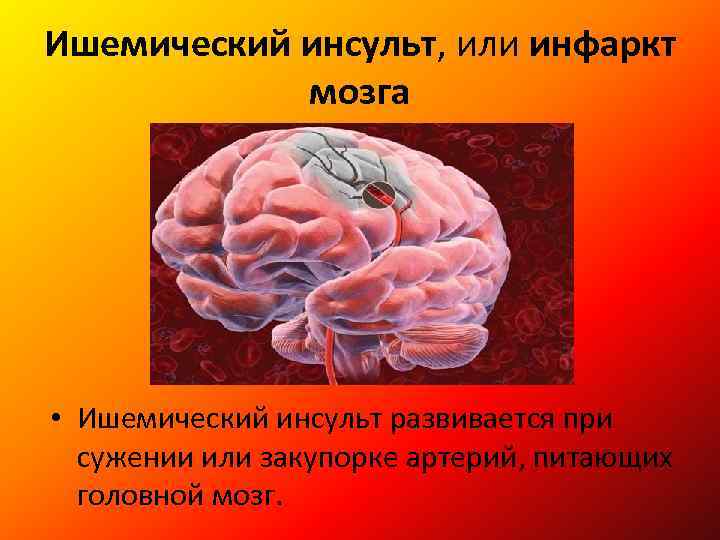

Ишемический инсульт левой стороны: симптомы и реабилитация